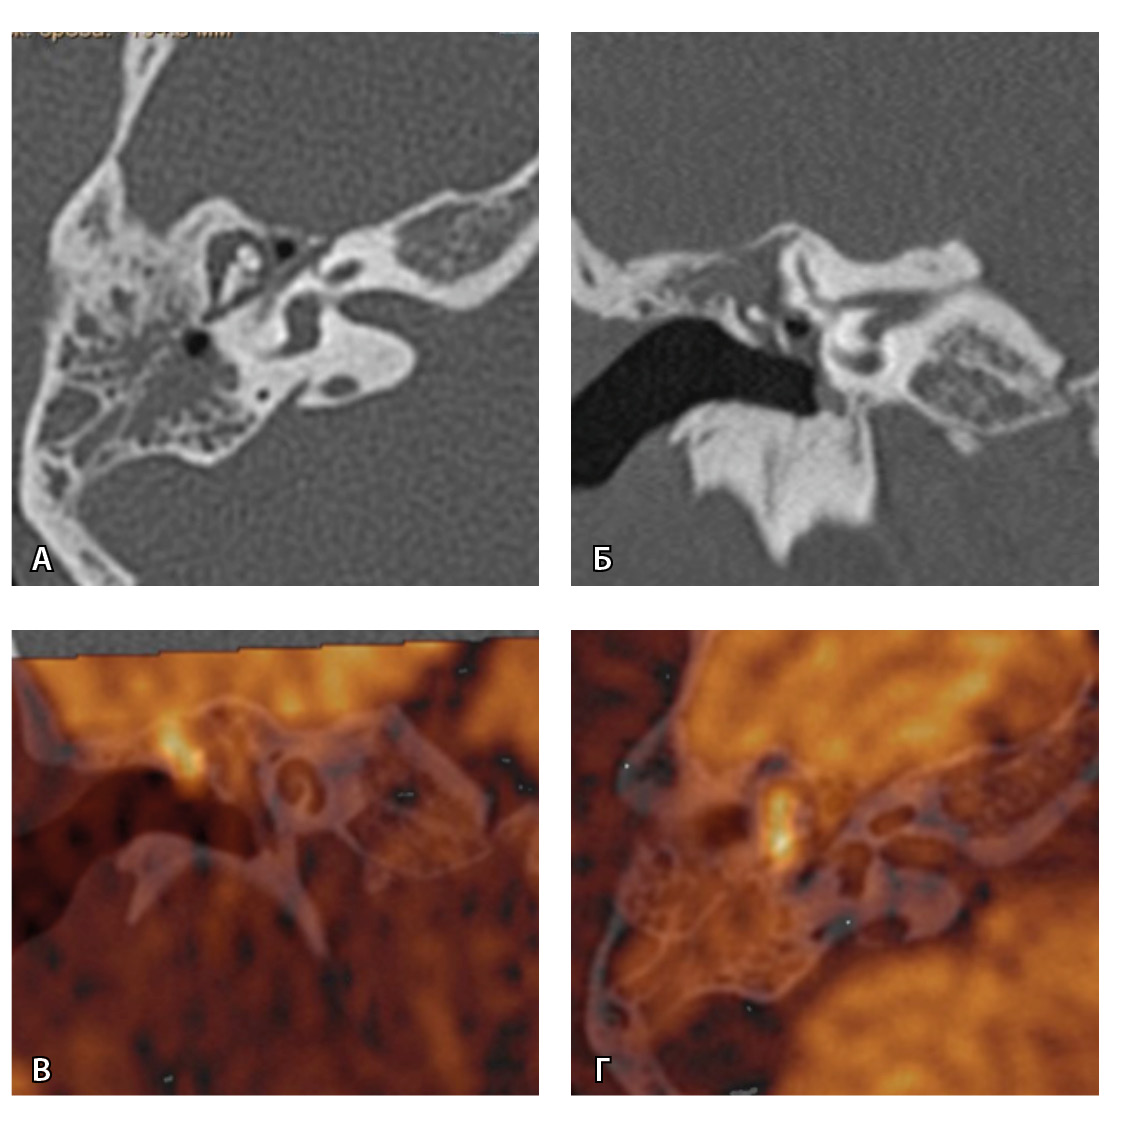

На рис. 3 и 4 показано расхождение данных КТ и МРТ.

Рис. 3. Хронический правосторонний средний отит. По данным компьютерной томографии (А, Б) нет ремоделирования барабанной полости, деструкции и смещения косточек, скутум сохранен, данных за холестеатому нет. При магнитно-резонансной томографии (В, Г) у того же пациента выявлен очаг высокого магнитно-резонансного сигнала, который при слиянии локализовался в области пространства Пруссака. Заключение и интраоперационно – холестеатома пространства Пруссака